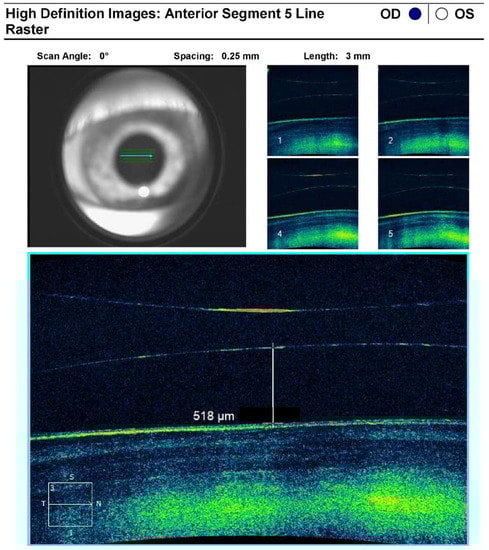

Diagnostic modalities included an Oculus Pentacam which reported the keratometry (K) indices for the flat and steep axis OD were 54.11 diopters (D) at 105° and 54.65 D at 15° respectively (Figure 1). Anterior Segment Optical Coherence Tomography highlighted an ICL vault of 518 μm (Figure 2). Biometry was performed using the Pentacam AXL, and the aim was to achieve a spherical equivalent of approximately −1.75 to −2.00 to avoid hyperopic results due to the patient’s severe keratoconus. A Johnson & Johnson Sensar AR40 monofocal 3-piece lens with a power of −9.5 with a predicted spherical equivalent of −1.76 using Barrett True K formula. Femtosecond laser use was attempted to perform parts of the surgery including capsulorhexis formation however this was unable to be completed due to significant scarring of the cornea, as well as CAI impeding adequate view. A 2.75 mm incision was made temporally and the ICL was extracted taking care to avoid damage to the cornea. Generous use of dispersive viscoelastic was helpful in ensuring optimal view throughout the procedure. Of note, the view was difficult thus proper magnification and lighting was ensured to aid with capsulorhexis formation. Nucleus disassembly was performed using a modified stop-and-chop technique and following cortex removal, the three-piece lens was injected using standard technique. Intracameral antibiotic and steroid were injected, and incisions were ensured to be watertight at the conclusion of the case.

Figure 2. Anterior segment optical coherence tomography measuring a normal vault, which is the distance between posterior surface of the ICL and anterior lens capsule.